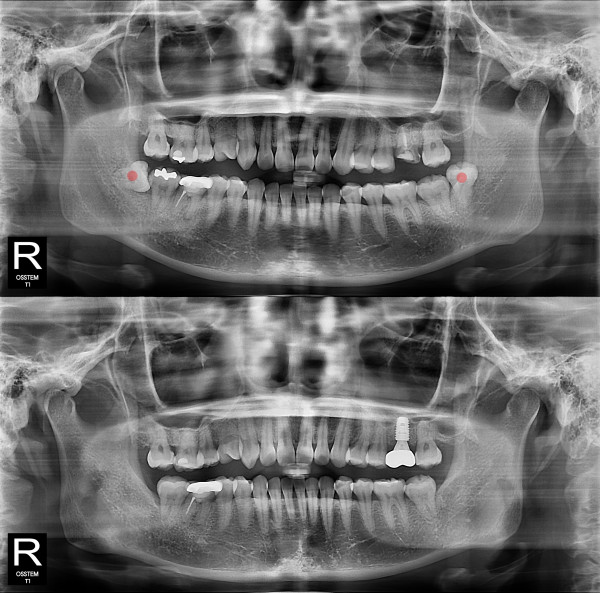

사랑니발치 부분 매복 사랑니

826e40416d712e6cd444a78bde93df4b_1767858043_7426.jpg